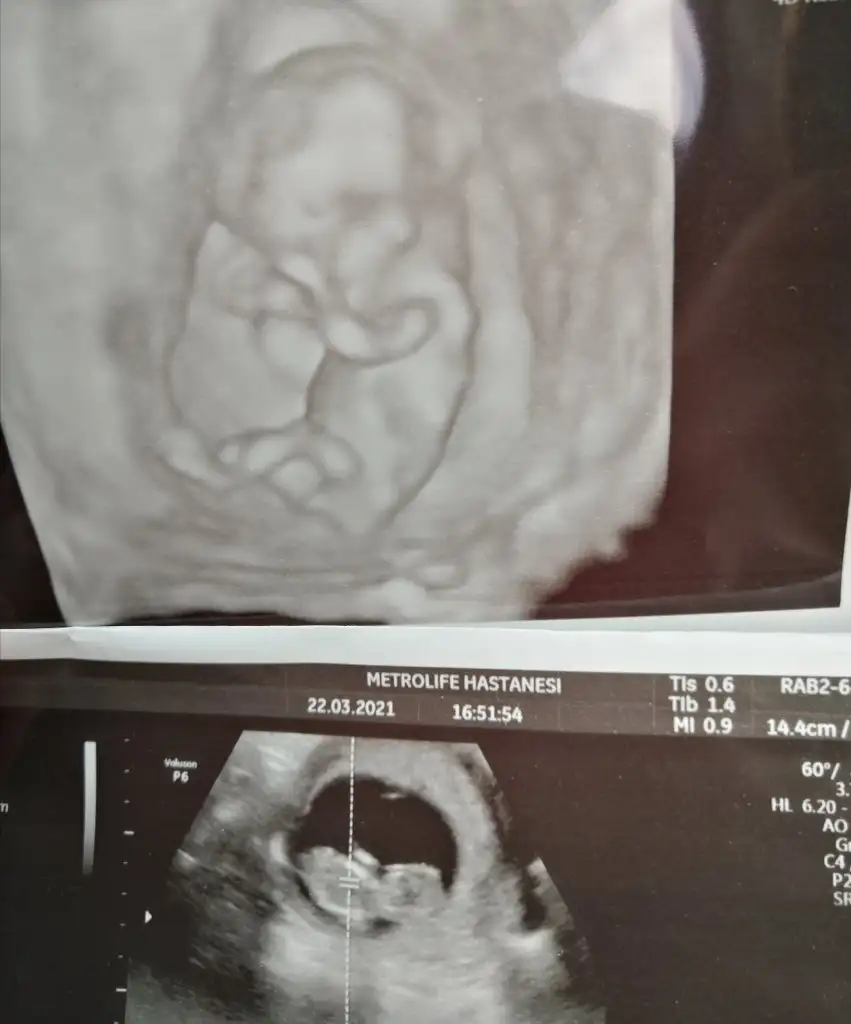

Ben normalde çarşamba görecektim 2 li test yapılacaktı ancak. Oksapar iğne yazdırmak için hastaneye gidince herhangi Bi doktordan randevu almam gerekti o da usg ye koydu ilacı da yazarken piya godan bebişi görmüş oldum

Metrolifeda hangi doktora gittin canım? Annem geçen orda Tuna hanıma gitmiş çok beğendi. Bu sefer geldiğinde bi tanışmak amaçlı görün dedi

Ay tunayı bende duydum iyimiş ama ben oksapar iğne yazdırma amaçlı sırası en boş doktora gittim Kenan gengeç hoca. Biz biraz ısrar ettik cinsiyet için o da bişeyler çıkarımda bulundu 2 hafta sonra tekrar bakılsın o zaman belli olur dedi. Ben normalde Bülent sezgine gidiyorum kendi kliniğine